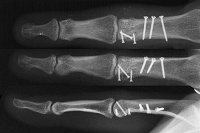

Clinical Example: Proximal phalanx bicondylar oblique volar coronal head fracture

This gentleman sustained a closed severe torsional injury of the right ring finger.

Xrays show a complex intraarticular fracture of the proximal phalanx head. There is a displaced spiral oblique longitudinal fracture with a second oblique coronal split through the articular surface of the radial condyle.